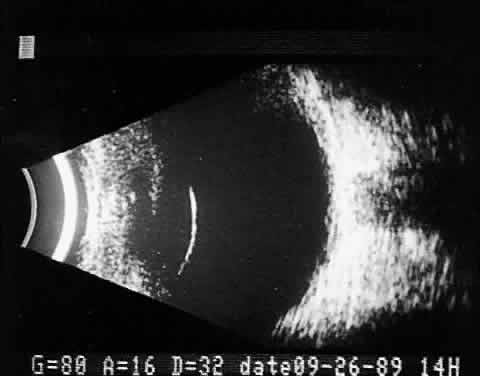

Fig. 16. Contact B-scan and simultaneous A-scan: “buried” choroidal metallic foreign body. Note strong B-scan gray-scale image and high A-scan echo amplitude.